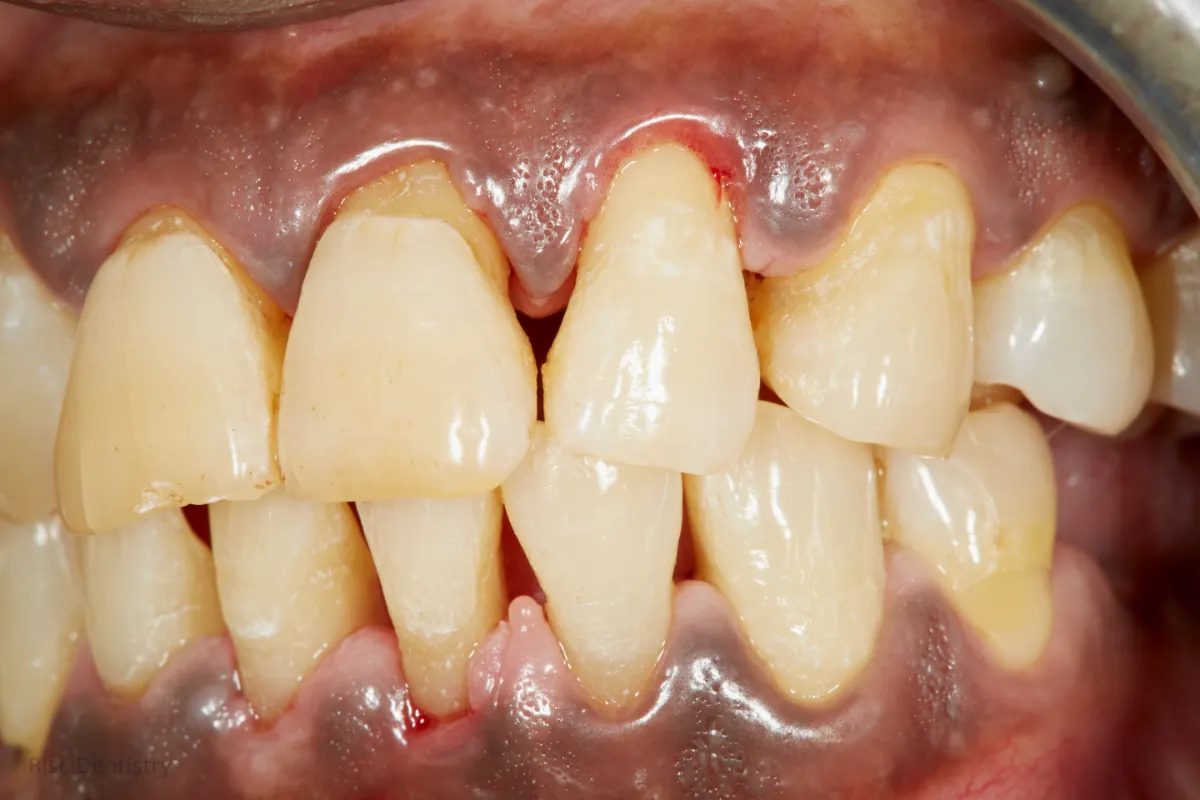

After Treatment

The change after gingivitis treatment is visible within days. Gums look pinker, feel firmer, and bleed less. Breath improves as bacteria are removed, and brushing becomes easier and more comfortable.